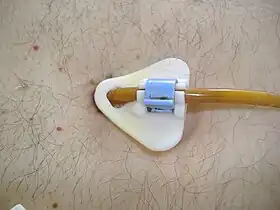

PEG tubes with a collapsible or deflatable bumper can be removed using traction (simply by pulling the PEG tube out through the abdominal wall).